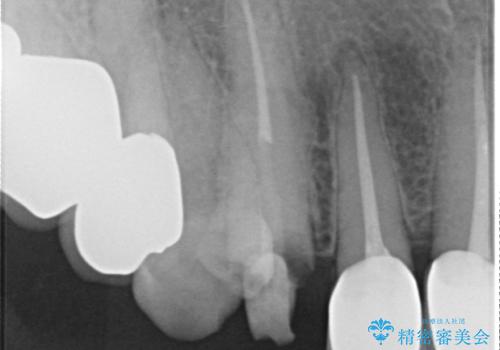

クラウン下に再発した深い虫歯 インプラントによる機能回復

- 定期検診で通院されていたところ、20年前に他院で治療した前歯のセラミック歯の下に深い虫歯が再発していることがわかりました。

前歯のインプラントを仕上げるには骨や歯ぐきの条件を整えることが肝要です。